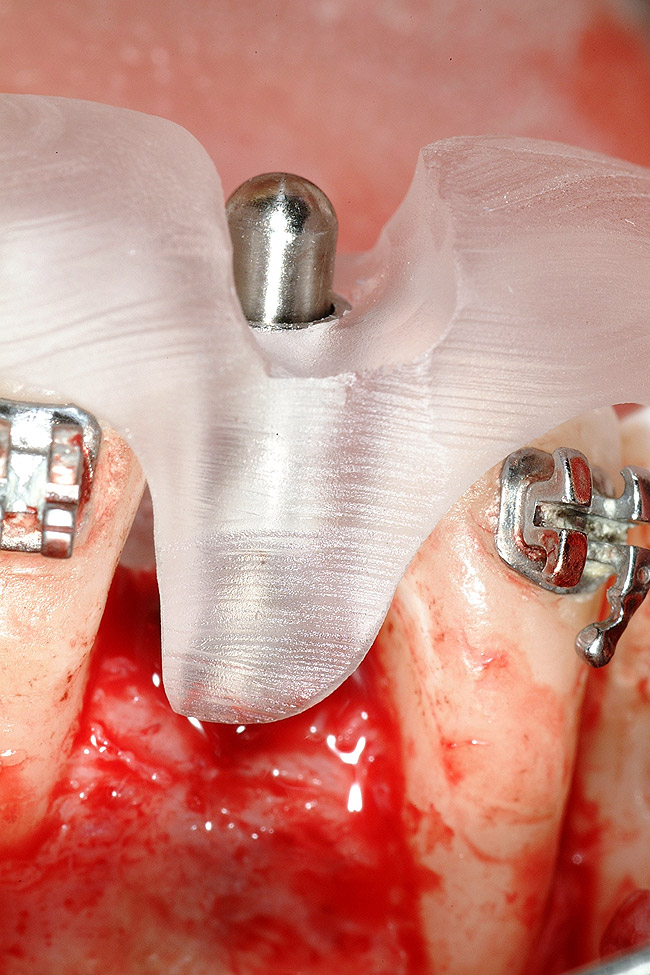

Figure 17  Tooth-supported SurgiGuide (Materialise Dental, Leuven, Belgium) (2 mm level) in place.

Figure 17

Figure 18  Implant placement with resulting facial dehiscence. Cortical perforations placed to promote angiogenesis.

Figure 18

Following the first goal of orthodontia—moving tooth No. 22 to a proper functional and anatomical position—a periodontal reevaluation was performed, demonstrating an improvement in short- and long-term tooth prognosis. At this time, the decision was made to abort continual extrusion of teeth Nos. 21 and 22, although some attachment level discrepancy remained between Nos. 21 and 22 (Figure 14). Implant diagnostics ensued and included mounted study models and a diagnostic wax-up. A scanning appliance was created to demonstrate the desired prosthetic outcome requirements, and the patient was referred for computed tomography (CT) scans. CT scan assessment demonstrated successful orthodontically directed GBR to allow implant placement (Figure 15 through Figure 16). Only minor GBR therapy would be needed and could be accomplished simultaneously with implant installation. Guided implant placement occurred, using an open flap approach (Figure 17). During surgery, root dehiscences were noted on teeth Nos. 21, 22, 24, and 25, as well as the anticipated dehiscence following implant placement at No. 23 (Figure 18). A positioning reference (index) was secured after implant placement to facilitate a provisional prosthesis at stage II surgery. Cortical perforations then were placed adjacent to the implant to encourage angiogenesis (Figure 18), and mineralized freeze-dried bone allograft enhanced with platelet-derived growth factor was placed over the dehiscences for purposes of guided tissue regeneration and GBR (Figure 19). A highly resorbable collagen membrane was placed to stabilize the allograft. The flap was coronally repositioned, and primary-intention wound healing was achieved (Figure 20 and Figure 21). Following 4 months of stage I surgery, implant uncovery and immediate provisionalization were performed in conjunction with connective tissue grafting. Final orthodontic tooth movement then ensued, using the implant as anchorage to optimize end-tooth movements, interroot separation, and the cuspid-protected occlusal scheme. A final impression then was secured, and a zirconia abutment (Figure 22) with an all-ceramic restoration was fabricated for the prosthetic phase completion of No. 23 (Figure 23 through Figure 25).